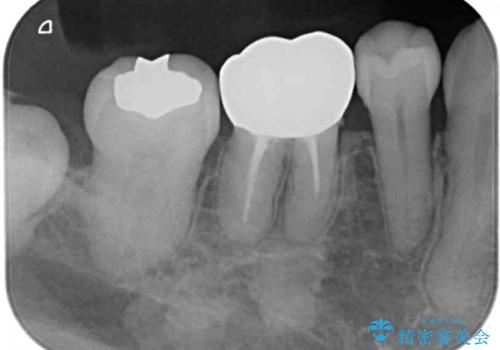

- 矯正治療後に、下顎奥歯の銀歯をすべてゴールドにすることを希望された患者様です。

セラミッククラウンやセラミックインレーによる補綴治療も提案しましたが、お友達にゴールドを自慢したいとのことで、ゴールドクラウンとゴールドインレーにて処置することとしました。

ゴールドは「白い歯」ではありませんが、銀歯の金属色とは異なり、非常にきれいな色合いが特徴です。

もちろん、適合が極めて良いという圧倒的メリットもゴールドクラウンやゴールドインレーの特徴です。